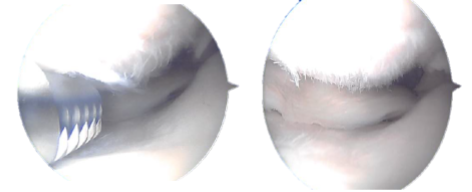

The knee scope was then inserted through a lateral working aperture in the left knee. A knee examination revealed patellofemoral arthritis, particularly in the distal medial patellar joint.

The trochlea had OA grade 1 to 2 changes, and the medial inferior patellar component had OA grade 3 to 4 changes. Chondroplasty of the inferomedial patellar aspect was combined with a medial femoral gutter synovectomy.

Intraoperative Arthroscopic images taken during operation